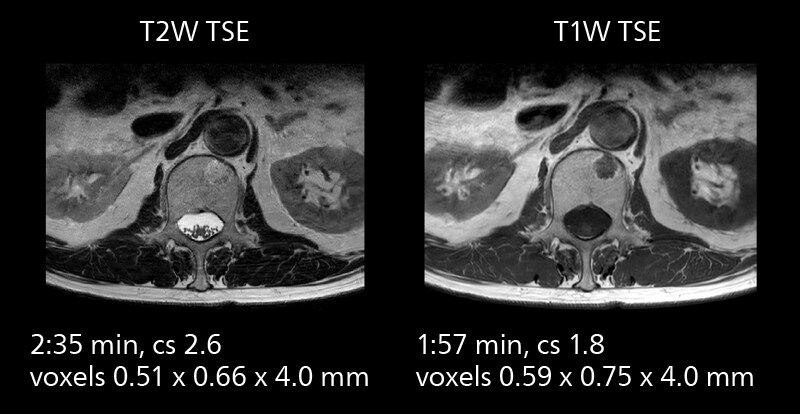

Examples of prostate imaging showing faster scan times and improved resolution illustrate the power of SmartPath to Elition X in this case of prostate cancer with PI-RADS score 4.